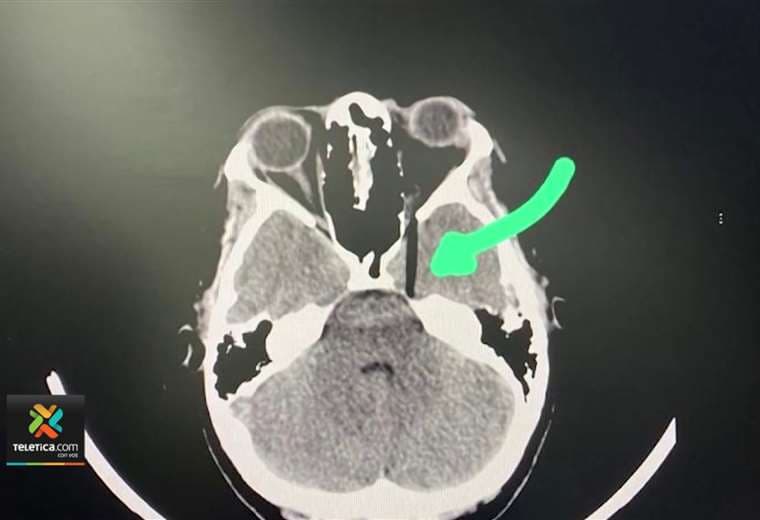

Para desgracia de la joven, debajo de las capas del queque había un pincho de bambú y se le incrustó en un ojo.

La hermana de la afectada descarta que sufriera daño cerebral por la incrustación del objeto, así como la pérdida del ojo.